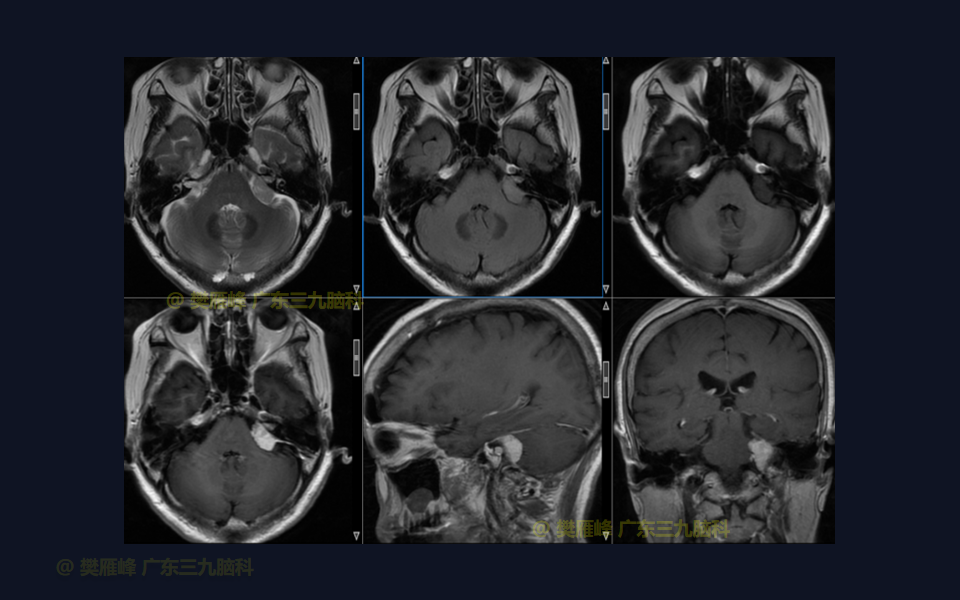

在这个二维手术视频中,展示了经枕下乙状窦后入路切除侵入内听道的桥小脑角脑膜瘤的方法。患者是一名66岁的女性,有2年左耳耳鸣伴听力下降,突发头晕半月,无面瘫病史,神经影像学显示左侧桥小脑角的侵入内听道从脑膜瘤。他接受了经乙状窦后入路保留面听神经的方法,术中肿瘤与脑干和面听神经轻度粘连,完全切除肿瘤。术后无面瘫,听力较术前明显改善,神经影像学显示肿瘤完全切除。我们展示了安全的颅神经和肿瘤切除术的细微差别和技术要点。

在这段手术视频中,展示了一名66岁女性的病例,他因左耳耳鸣伴听力下降2年余,突发头晕半月发现的左侧桥小脑角区脑膜瘤